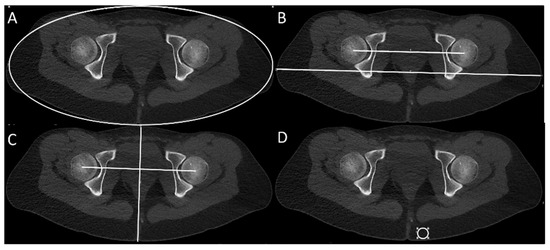

2.5. Measurement of Body Volume Parameters, CNR and DC